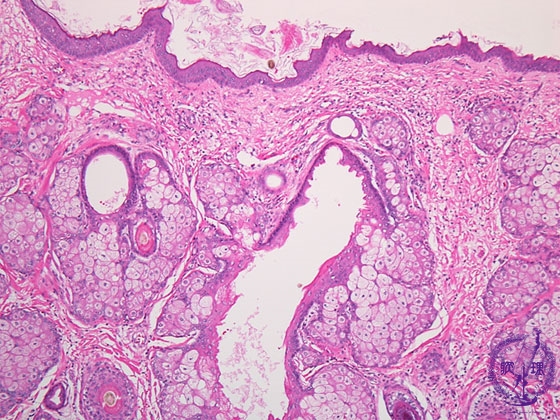

- ★(9)Ovarian teratoma(Dermoid cyst)

Histology (HE stain, low power): Mature cystic teratoma (dermoid cyst). Epidermis (yellow dotted line) or follicles (red dotted line) and sebaceous glands (blue dotted line) as skin appendages are apparent.